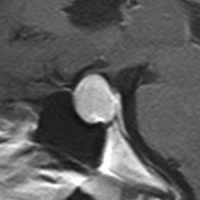

下垂体腺腫からの出血

- 下垂体腺腫からの出血はとても多いです

- 出血があるからと言って,手術しなければならないわけではありません

- 出血は自然に溶けて吸収されるので,ほっておくと小さくなります

- 出血の程度がひどくて,下垂体卒中と言われるなかでも強い症状があるときだけは手術をします

頭痛で発症して,左側の画像のような小さな腺腫が見つかりました。真っ白に見える部分は腫瘍の内部での出血です(内出血)。わずかな出血なので自然に吸収されますから,なにもしないでほっておきました。1年後に再出血(右側の画像)して,軽度の視野欠損がでました。仕方がないので手術で腺腫と出血を摘出しました。